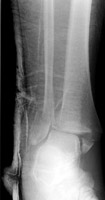

A | Mortise view of the ankle. This demonstrates a minimally displaced fracture of the medial malleolus of the distal tibia. |